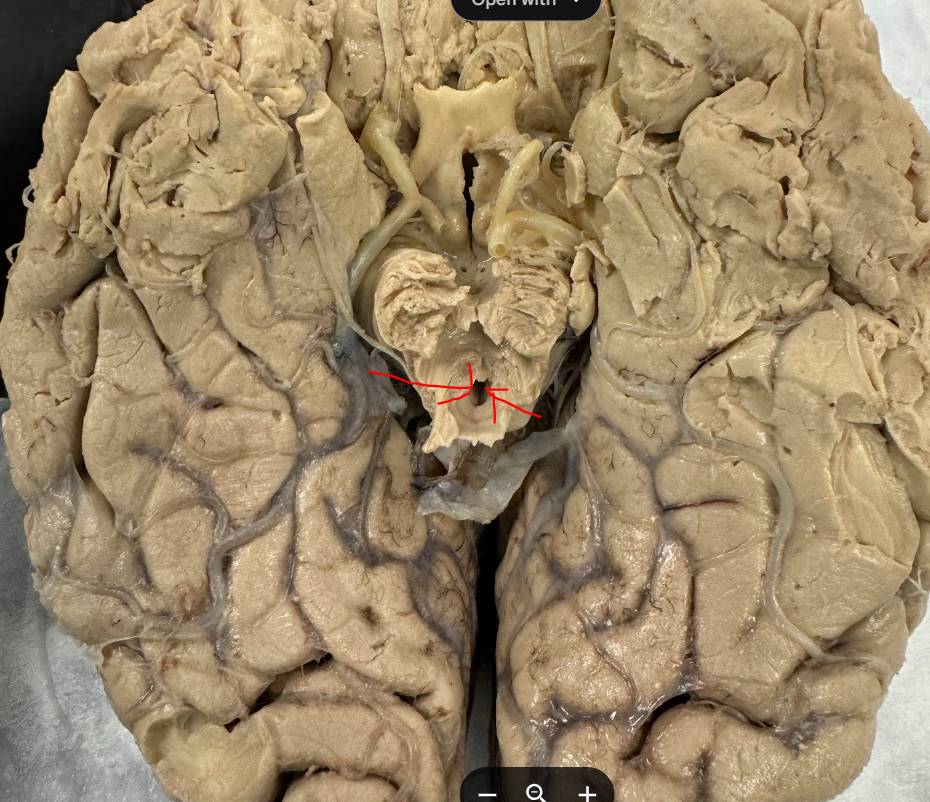

anterior cerebral artery